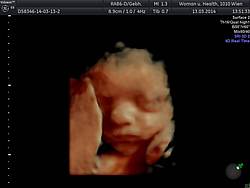

30. bis 34. SSW

Wellbeingschall mit Wachstums- und Gewichtskontrolle des Feten, Bestimmung von Fruchtwassermenge, Plazentasitz und –struktur sowie Kontrolle von Nabelschnurdurchblutung, Harn und Blutdruck.

35. bis 38. SSW

Kontrolle der Kindslage, des Wachstums, der Fruchtwassermenge und Nabelschnurdurchblutung.

Bei Bedarf Blutabnahme von Toxoplasmose und Zytomegalie. Oftmalig vaginaler Streptokokkenabstrich.